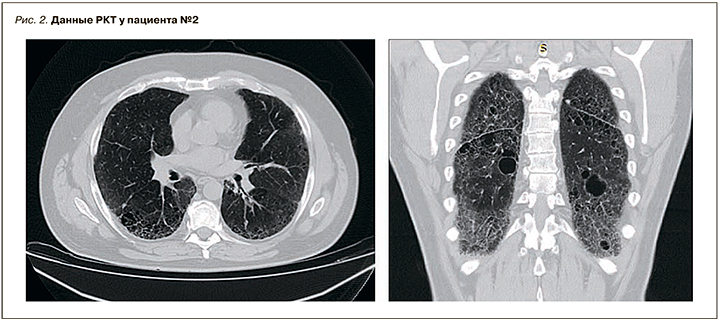

В 2016 г. заметил деформацию ногтевой пластины, «округление». 14.03.2019 на плановой флюо-рографии отмечена патология легочной ткани, направлен на РКТ органов грудной клетки. РКТ от 16.03.2019 выявила КТ-признаки диффузного интерстициального процесса в легких, вероятен фиброзирующий альвеолит. Для дообследования и лечения госпитализирован в пульмонологическое отделение.

При осмотре кожные покровы и волосы светлые, глаза светло-голубые. Грудная клетка обычной формы, симметрично участвует в акте дыхания. Перкуторно над легкими выслушивается звук с коробочным оттенком, аускультативно дыхание жесткое, выраженная крепитация в нижних отделах с обеих сторон. Частота дыхательных движений (ЧДД) – 19 в минуту, SpO2 – 97%. Результаты РКТ органов грудной клетки: пневматизация легочной ткани неравномерно снижена, междольковый интерстиций неравномерно уплотнен. По легочным полям образования округлой и овальной формы с относительно четким контуром, наибольшим размером в S4 справа 15×12 мм, в S6 справа 6 мм, в S2 слева 14×11 мм, в S2 слева субплеврально 9 мм, очаги уплотнения до 3–4 мм. По легочным полям видны множественные буллы до 31 мм (рис. 2).